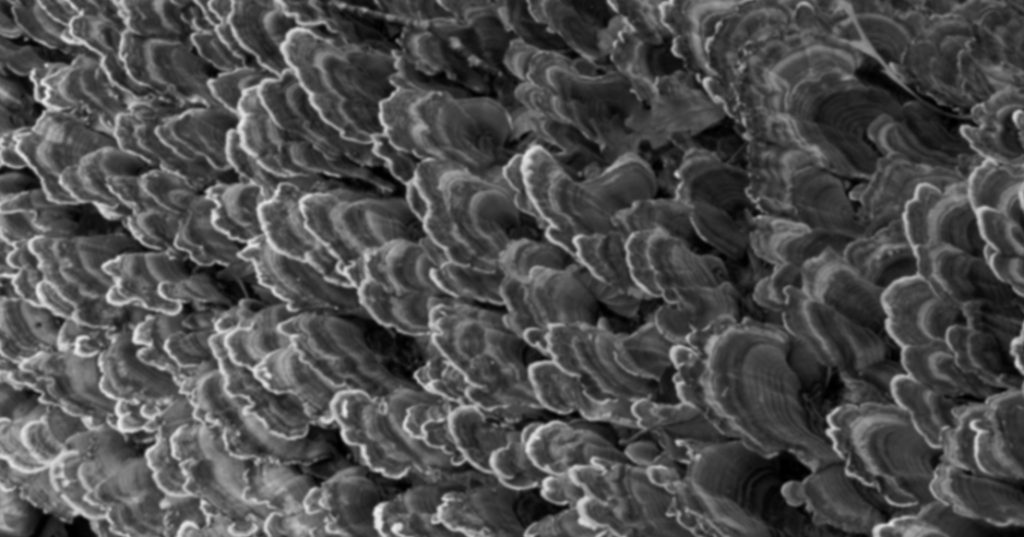

Opaquers are highly pigmented resins containing metal oxides responsible for opacification. These metal oxides are usually titanium or aluminum oxide and achieve increased opacity by increasing absorption and scattering light within the resin. Opaque chromatics may be sub-divided into: